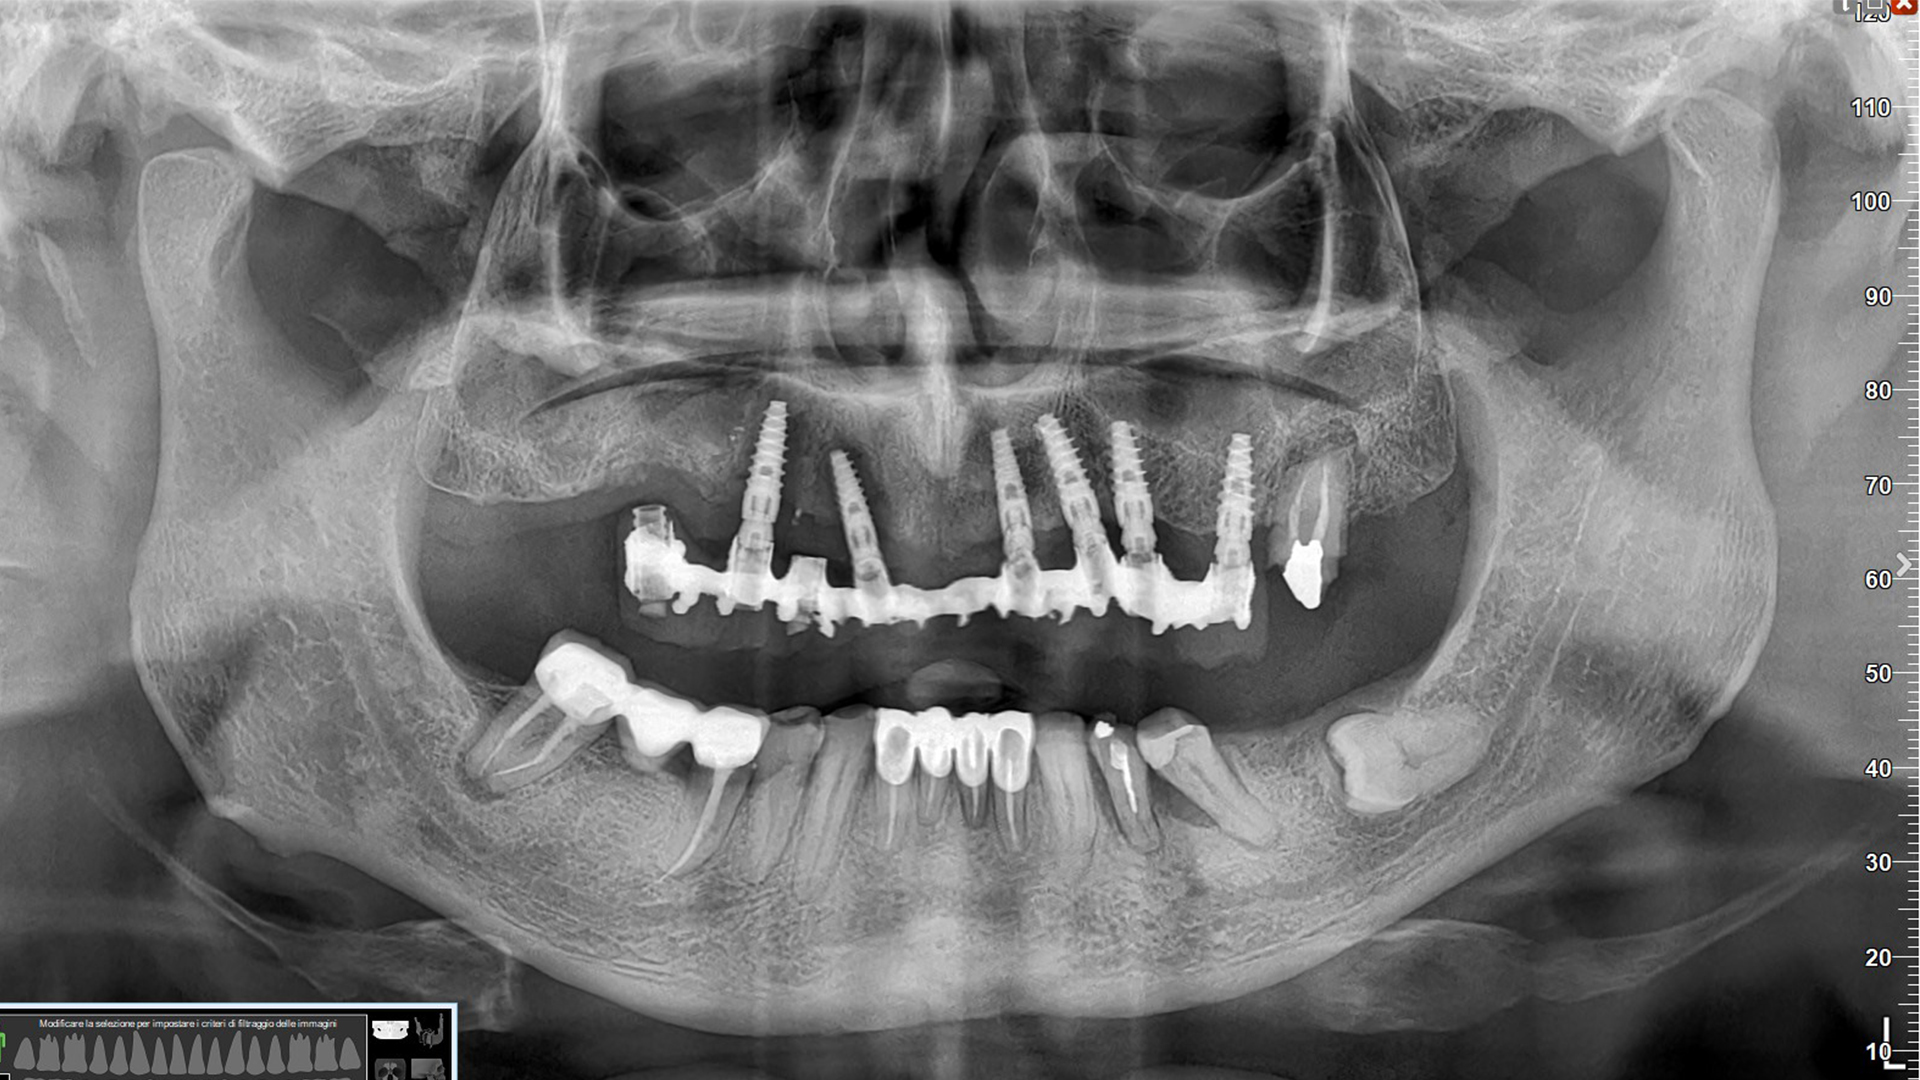

La situazione protesica precedente è questa e ti prometto che a breve pubblicherò anche la soluzione protesica del caso.